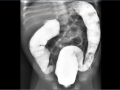

Hemorragia adrenal em recém nascido

Set de 2024.